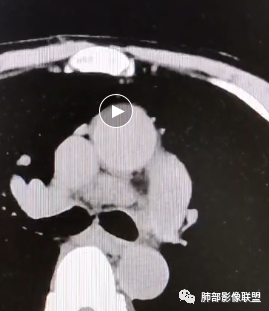

看一下影像,肺动脉粗大,大于升主动脉

从肺动脉的主体分析:左肺动脉好像起始部就开始狭窄。

现在给的图像:是鼠尾状狭窄,而不会局部膨隆,远端细小那种。

右侧的肺动脉增粗肯定与代偿有关。

现在的问题是自左肺动脉狭窄的原因:是急性栓塞?炎性病变?慢性血栓?